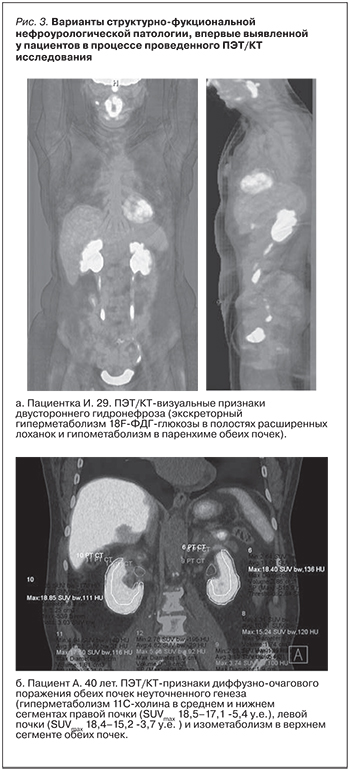

На рис. 3. представлены некоторые варианты структурно-фукциональной нефроурологической патологии, впервые выявленной у пациентов в процессе проведенного ПЭТ/КТ-исследования.